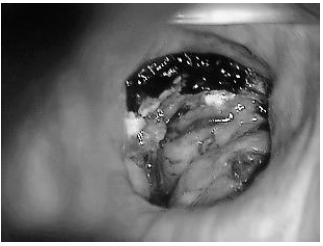

Paciente de 50 anos, histórico de hipertensão

arterial sistêmica, encaminhada por alteração

em exame citopatológico. Foi realizado

colposcopia, com o achado representado na

Figura 1, exposta abaixo.

Figura 1. Exame colposcópico. Fonte: Federação Brasileira das Associações de Ginecologia e Obstetrícia (FEBRASGO). Manual de Orientação em Trato Genital Inferior e Colposcopia. 2010